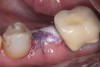

Fig 12. (Case 2) Tooth No. 9 was extracted; the buccal plate was dehisced.

Figure 12

Fig 13. Flap elevated 6 months after d-PTFE barrier and bone graft were placed; the barrier was removed after 4 weeks. This photograph shows the buccal plate regenerated.

Figure 13

Fig 14. An implant was inserted in regenerated bone.

Figure 14

All three studies7-9 addressing defective alveolar ridges reported a positive finding with respect to healing, which facilitated implant placement in all monitored patients. In addition, the four cases presented by the current authors (Figure 1 through Figure 25) attained excellent results with d-PTFE plus an alloplastic bone graft (Puros) when treating buccal wall defects.

Case Presentations

The four presented cases shown in Figure 1 through Figure 25 were all treated in a similar manner as outlined in detail in the captions for the first case (Figure 1 through Figure 11). In all four cases, teeth with pathosis were removed, buccal and lingual flaps were elevated, and sites were surgically debrided. A Cytoplast d-PTFE barrier was sized and inserted usually under the buccal flap, the bone graft was added, the barrier was then tucked under the lingual flap, and the flaps were sutured. Bone grafts were used in all of the cases, because buccal bony plates were resorbed and the bone graft helped support the barrier.